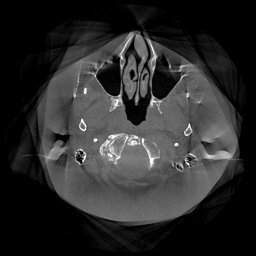

III-D Real Clinical Data Experiment

The experimental results on clinical head data are shown in Fig. 4. The reference images were reconstructed using the fast iterative shrinkage-thresholding algorithm (FISTA) with total variation regularization from non-truncated projection data. In the WCE reconstructions (Fig. 4(b)), severe truncation prevents accurate recovery of anatomical structures outside the FOV. Despite being trained solely on simulated data with a domain gap, all deep learning models can restore a substantial portion of the missing anatomy. Among them, the diffusion-based methods recover soft-tissue boundaries more faithfully than the conventional deep learning approach FBPConvNet, highlighting their stronger image generation capability. However, cDDPM reconstructions exhibit more noticeable noise than those from other methods, consistent with the simulated data results. The patchDiffusion model introduces artifacts within the FOV, likely due to its patch-wise processing strategy. While I2SB shares the same limitations as other diffusion models in perfectly restoring soft-tissue detail, it produces fewer residual noise patterns and fewer artifacts within the FOV boundaries. Overall, Fig. 4 demonstrates the strong efficacy of I2SB in reconstructing real CBCT data.